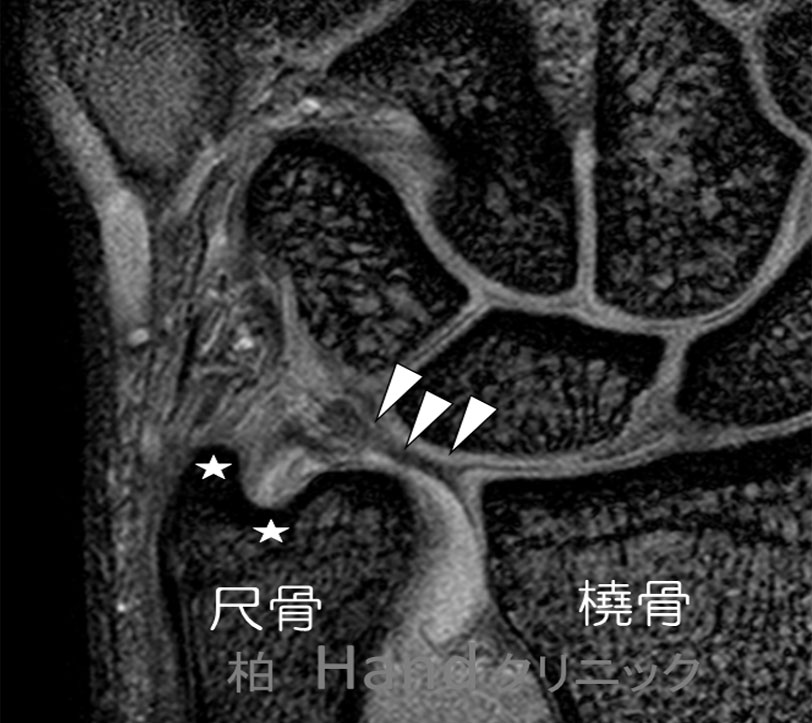

また、MRIが有効です。

図は正常者のMRIマイクロスコピーコイル使用時の画像です。☆印がTFCCの尺骨付着部です。

この靭帯がきれるとビデオのようになります。その他、関節造影検査、造影後CT検査等があります。